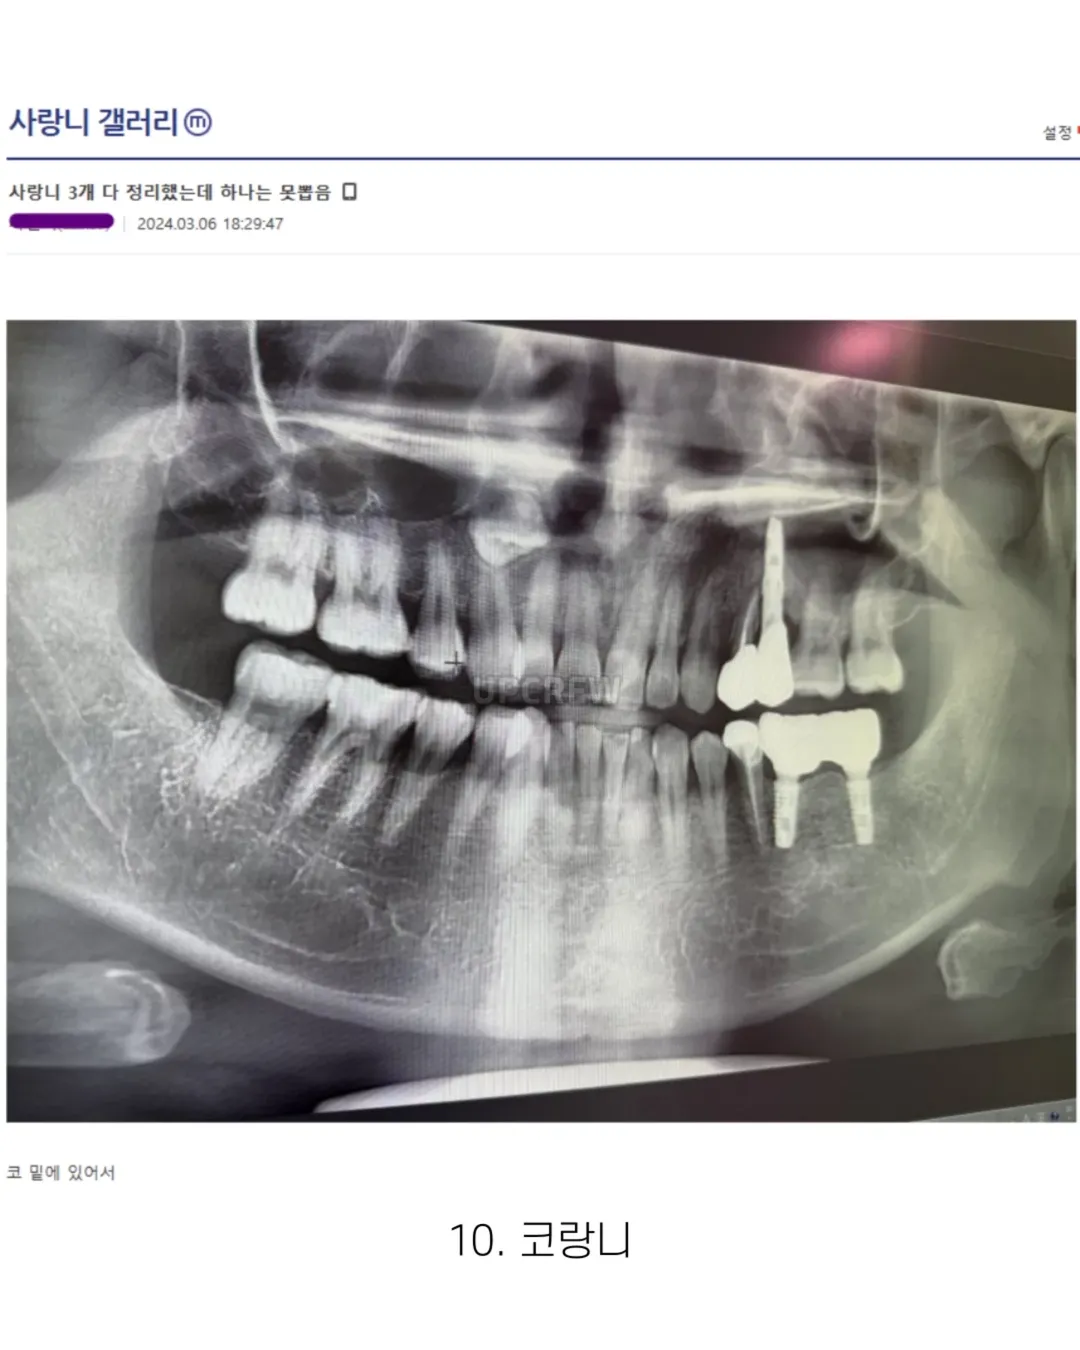

사랑니 갤러리의 특이한 사랑니들 (약혐 주의)

하.. 나는 애매한데 사랑니가 코 근처에서 둥둥 떠있음..ㅠ 왜 이렇게 된건지는 모르겠는데 치과의사쌤이 얼굴뼈 안쪽에 물이차서 사랑니가 같이 올라가버려서 뭐 어떻게 할수가 없다고 함..ㅜ 불편한거 없으면 괜찮을 것 같은데 나중에 빼고싶으면 위험 감수하고 대학병원가서 주사로 입천장 뚫어서 물 다 빼내고 사랑니가 밑으로 내려오길 기도하고 내려오면 수술해야한다고 하더라 레전드